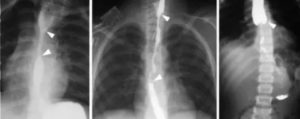

Рентгенологическое исследование позволяет обнаружить инородное тело, если оно рентгеноконтрастное, косвенные признаки аспирации нерентгеноконтрастного инородного тела (ателектаз, острая эмфизема сегмента, доли или целого легкого), маятникообразное смещение тени средостения при форсированном дыхании (при вдохе тень средостения смещается в сторону поражения, при выдохе — в здоровую сторону).

Особую сложность представляют случаи с неорганическими телами, ведь их не видно на стандартном рентген-снимке.

Однако даже тогда можно заметить косвенные признаки: ателектаз, эмфизему и очаговые изменения в легочной ткани.